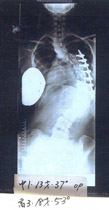

平成19年2月13日

60度

平成22年6月23日

正常範囲度数云われず

聖隷佐倉市民病院60度

きれいな身体と肋骨変形も改善

レントゲンは正面からです